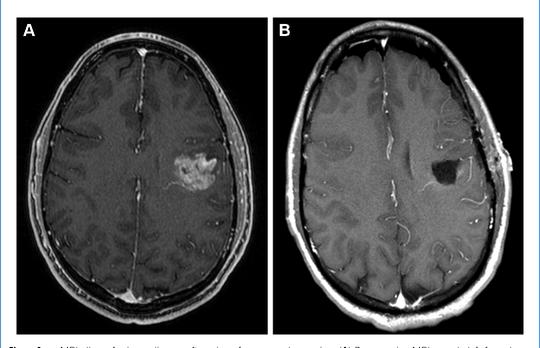

La FDA y el HC aprobaron VORANIGO en agosto de 2024 para el tratamiento de tumores cerebrales raros llamados astrocitomas y oligodendrogliomas Estas formas raras de cáncer tienen una mutación llamada IDH1 o IDH2 Servier apoyó el desarrollo de Voranigo, que bloquea la acción de las proteínas IDH1 o IDH2, reduciendo el crecimiento de las células cancerosas. La presentación incluyó los resultados del ensayo INDIGO (NCT04164901). En este ensayo clínico, Voranigo redujo la progresión de la enfermedad en más de la mitad en comparación con el placebo (28% frente al 54%). Además, durante el estudio, los pacientes tratados con Vorangio no alcanzaron el tiempo medio hasta el tratamiento posterior (TST). Sin embargo, los pacientes que recibieron placebo alcanzaron el TST a los 18 meses. Consulte más detalles sobre el glioma, los tratamientos actuales y su impacto en la calidad de vida del paciente y su entorno en el artículo de la página 19.

Tratamiento del glioma IDH en la era VORANIGO

En agosto de 2024, Health Canada aprobó Voranigo para el tratamiento de astrocitomas y oligodendrogliomas (Figura 3) Servier apoyó el desarrollo de Voranigo, que bloquea la acción de las proteínas IDH1 o IDH2, reduciendo el crecimiento de células cancerosas La presentación incluyó los resultados del ensayo INDIGO (NCT04164901) Análisis anteriores han demostrado que los inhibidores de IDH son más activos en pacientes con gliomas menos avanzados La adquisición de mutaciones adicionales puede explicar esta observación durante la progresión [32-33] Cuando la enfermedad progresa, un cóctel de medicamentos dirigidos a diferentes mutaciones es más eficaz que la monoterapia en general

Se han probado tres inhibidores de IDH y Voranigo proporcionó los mejores resultados debido a su capacidad superior para penetrar en el cerebro [35]. Estos ensayos sentaron las bases para el ensayo INDIGO, cuyo objetivo era probar la eficacia de vorasidenib en el tratamiento inicial de gliomas de bajo grado. Los pacientes con gliomas de bajo grado inscritos en INDIGO se sometieron a cirugía y fueron observados activamente durante uno a cinco años. Presentaban signos de enfermedad residual o recurrente. Vea más detalles del diseño del ensayo clínico en la Figura 4.

En este ensayo clínico, Voranigo redujo el riesgo de progresión de la enfermedad en un 61 % en comparación con la estrategia de observación y espera (placebo) (Figura 5) Además, durante el estudio, los pacientes tratados con Vorangio no alcanzaron el tiempo medio hasta el siguiente tratamiento (mTTNI) Sin embargo, los pacientes que recibieron placebo alcanzaron el mTTNIalos17,8meses(Figura6).

Se trata de una terapia oral, por lo que resulta más cómoda que la radioterapia Las toxicidades observadas fueron leves y comparables entre los grupos de Voranigo y placebo Tomar Voranigo no afectó significativamente la calidad de vida de los pacientes. Para la mayoría de los pacientes, es un desafío estar en observación activa cuando se sabe que la enfermedad sigueahíy quevaaprogresar

Por su eficacia y tolerabilidad, Voranigo puede sustituir a la observación activa para retrasar la progresión lo máximo posible. Además, el uso de Voranigo puede informar y retrasar la necesidad de recibirradioy quimioterapia.